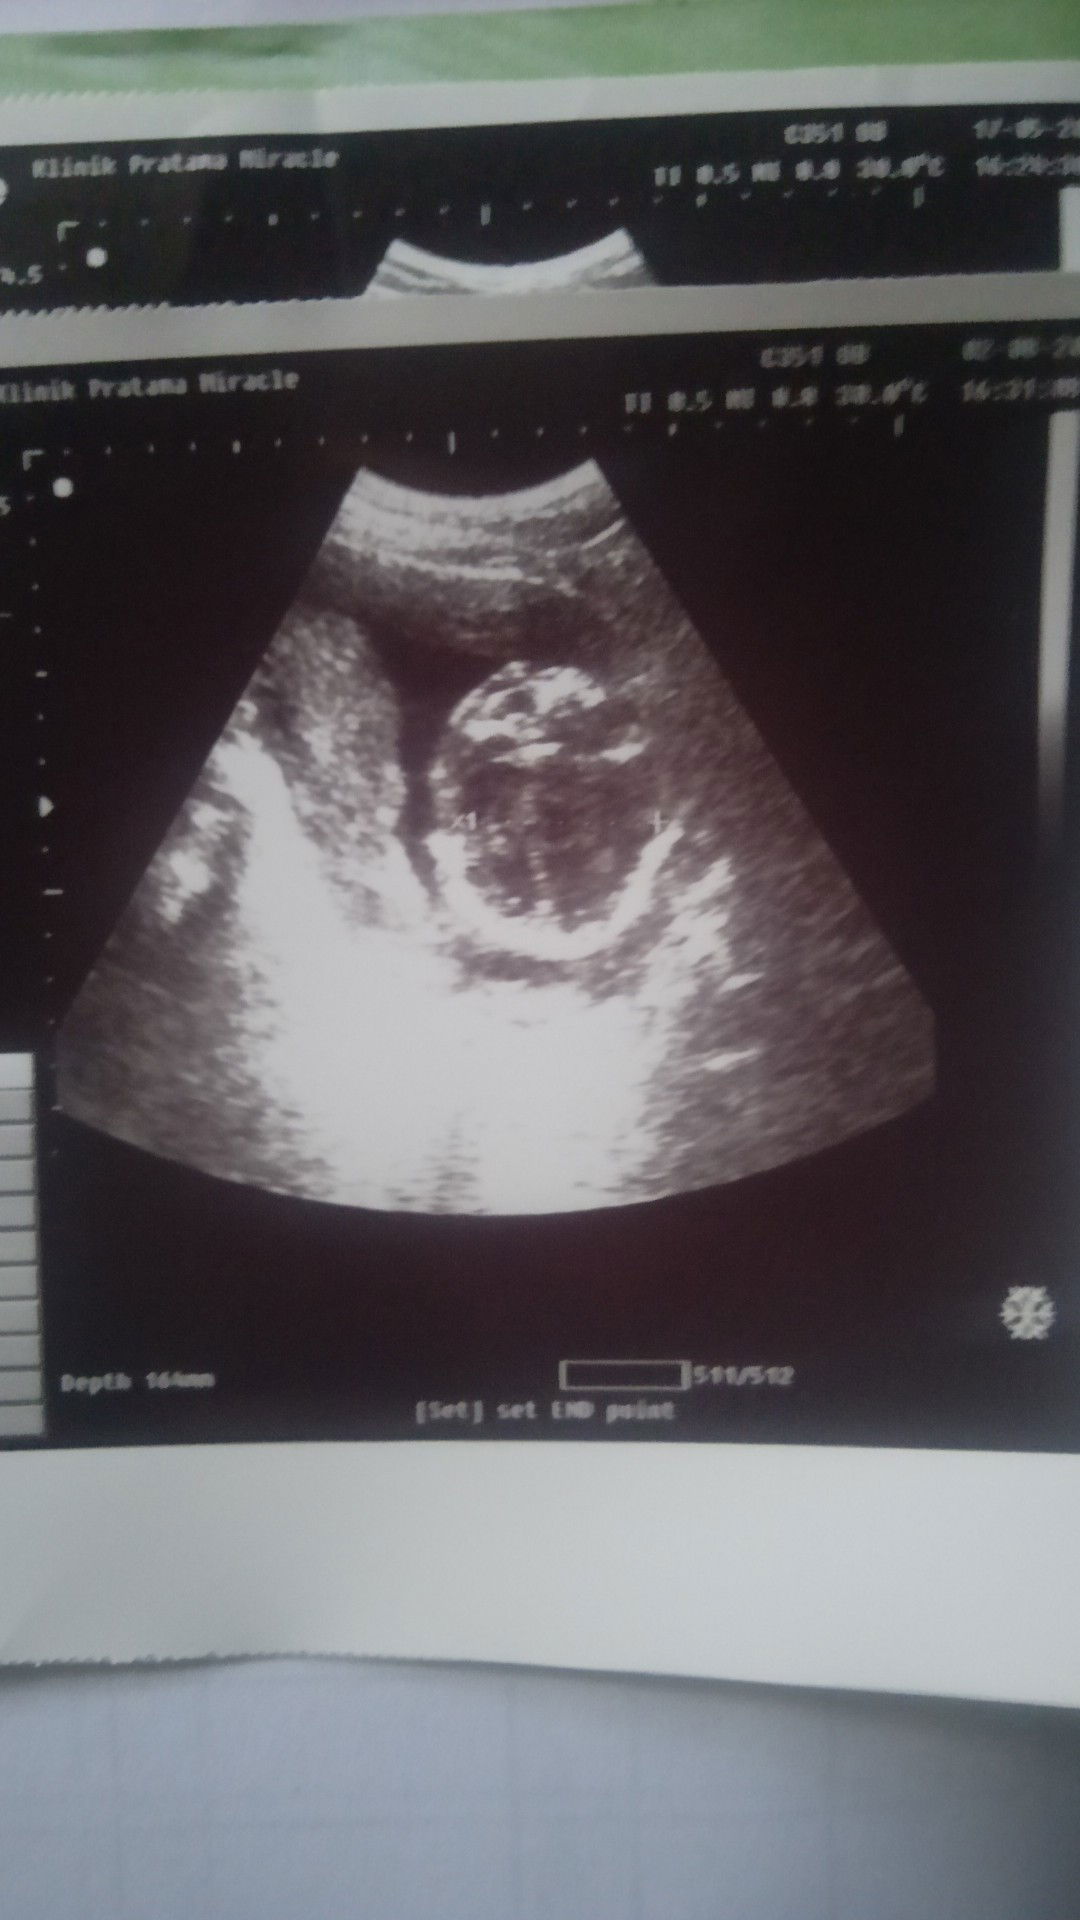

assalamualaikum Bun mau nanya kalo lagi hamil tapi banyak keputihan gimana ya wajar ga makasih

Mendamba seorang anak